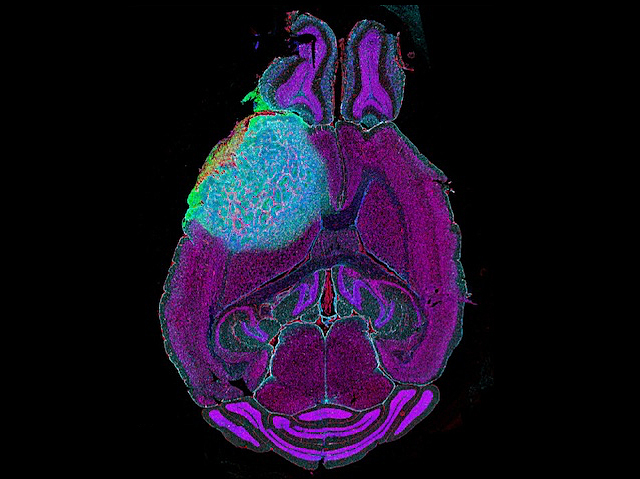

Recurring from Scars

A treatment called CSF-1R inhibition for the aggressive brain tumour glioblastoma showed promise in experiments in mice but tumours recurred, and from regions adjacent to scarring or fibrosis. This study analyses the genetic and molecular characteristics of the tumour, its microenvironment and regions of fibrosis after treatment in tissues from patients and experimental models and finds the fibrotic response potentiates the recurrence